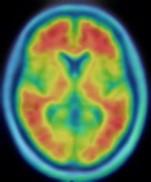

Twenty years in, all participants underwent MRIs and positron emission tomography (PET) scans of their brains to measure levels of amyloid beta protein accumulated in the brain, a standard marker of Alzheimer's disease. The average PET scan score indicating the amount of amyloid beta protein in the brain after being compared with a part of the brain where amyloid beta doesn't accumulate was 1.2. Some 171 participants were categorized as having elevated values greater than this standard, and the remaining participants were assigned to the nonelevated amyloid beta values category.